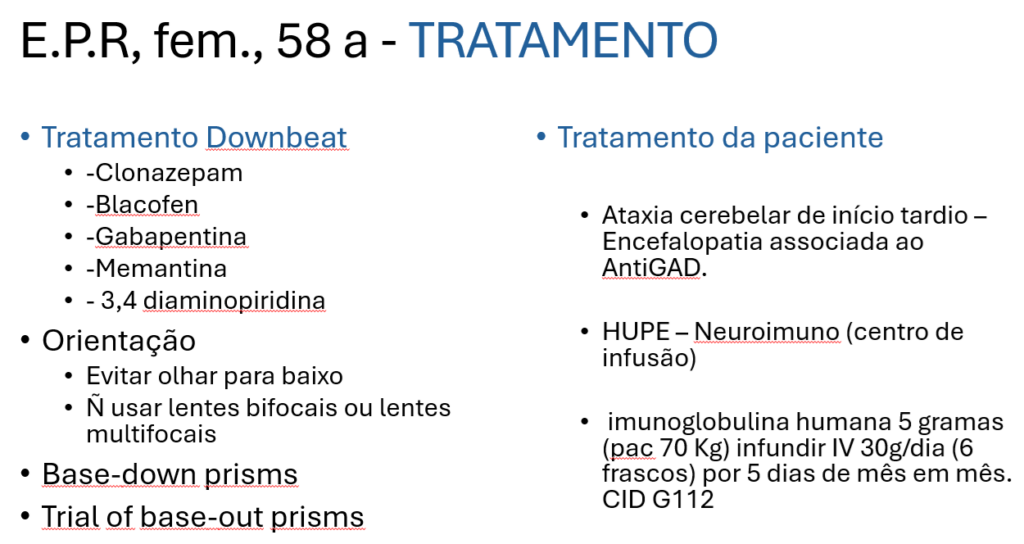

Coloco abaixo do lado esquerdo as opções de tratamento utilizadas no NEVI e do lado direito o tratamento indicado para esse caso.